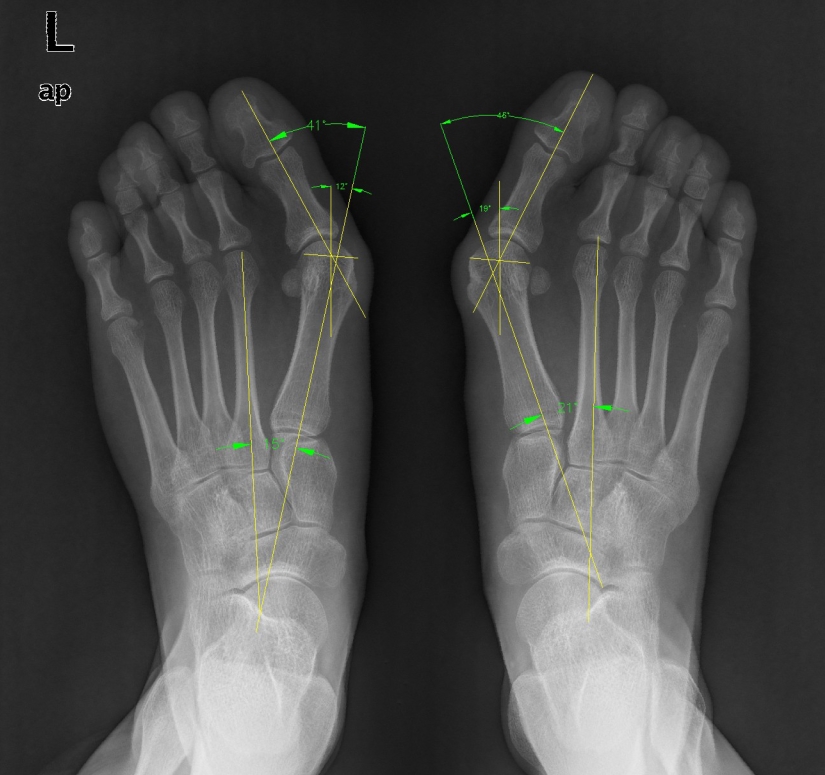

对于保守治疗不能缓解症状者,则建议行手术矫正拇外翻。目前,临床上矫正拇外翻的手术方法有近百种之多,但没有一种手术方法适合所有的拇外翻患者,所以应根据每个患者的具体情况选择合适的手术方法。通常要根据X线测量结果及临床表现,对于轻、中度的拇外翻(拇外翻角小于40°,第1、2跖骨间夹角小于20°),可采用跖趾关节外侧软组织松解、跖骨头内侧骨赘切除、第1跖骨头颈部或近端截骨外移手术进行矫正。对于重度拇外翻(拇外翻角大于40°,第1、2跖骨间夹角大于20°),除常规行外侧软组织松解和内侧骨赘切除外,还需行第1跖骨干或基底截骨术。对于拇趾跖趾关节已有骨性关节炎的患者,多采用跖趾关节融合术或人工关节置换术。对于合并跖楔关节过度活动患者,则需行跖楔关节融合术。

典型病例二:24岁女性,重度拇外翻,术前双足拇外翻6年,伴跖趾关节疼痛1年余,严重影响工作。行双侧软组织松解+内侧骨赘切除+跖骨头截骨矫形术,术后外观恢复满意,患者活动功能完全恢复正常。

(术前X线片)

(拇外翻矫形术后X线片)